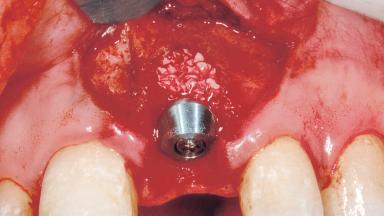

Immediate Placement of an Implant in a Maxillary Left Central Incisor Site

Bone Augmentation Horizontal|Simultaneous

Augmentation Materials Xenogenous|Membrane

Soft Tissue Grafting Simultaneous

Placement Protocol Immediate implant placement

Socket Integrity Damage to one or more bone walls

Bone Volume Damage to one or more socket walls